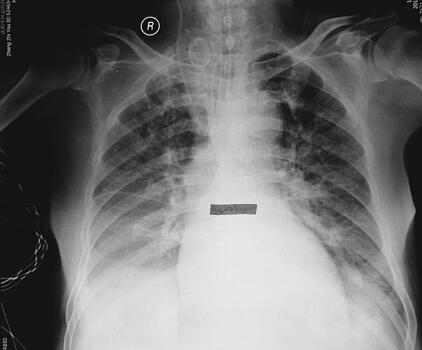

患者入院时血象明显高于正常,同时痰黄量多,体温最高38℃,给予头孢哌酮-舒巴他钠抗感染,同时经口气管插管、呼吸机辅助呼吸以及解痉平喘、祛痰等治疗。患者血象逐渐呈下降趋势,最高体温37.8℃,胸部影像亦较前明显好转,3月1日拔除经口气管插管(图3、图4)。

图3 入院第4天胸片:双肺渗出较前减少